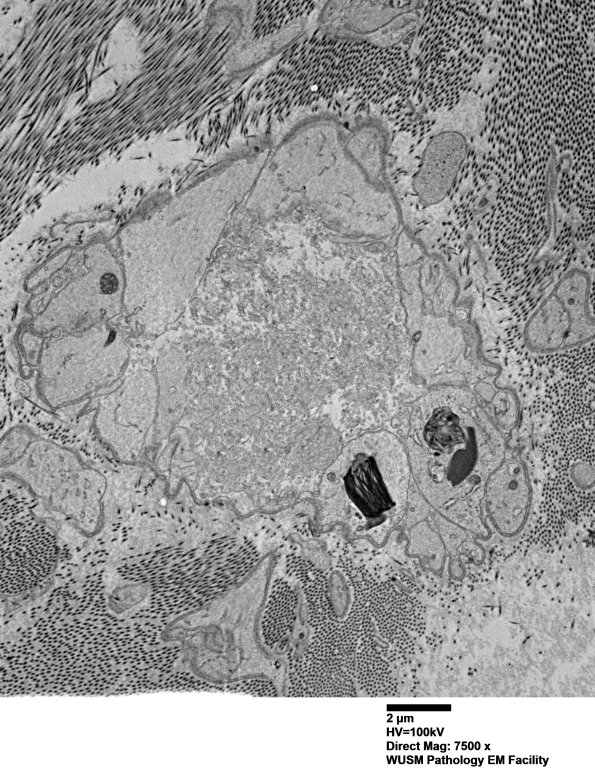

This spheroid is dominated by coarse tubulovesicular elements. (electron micrograph)